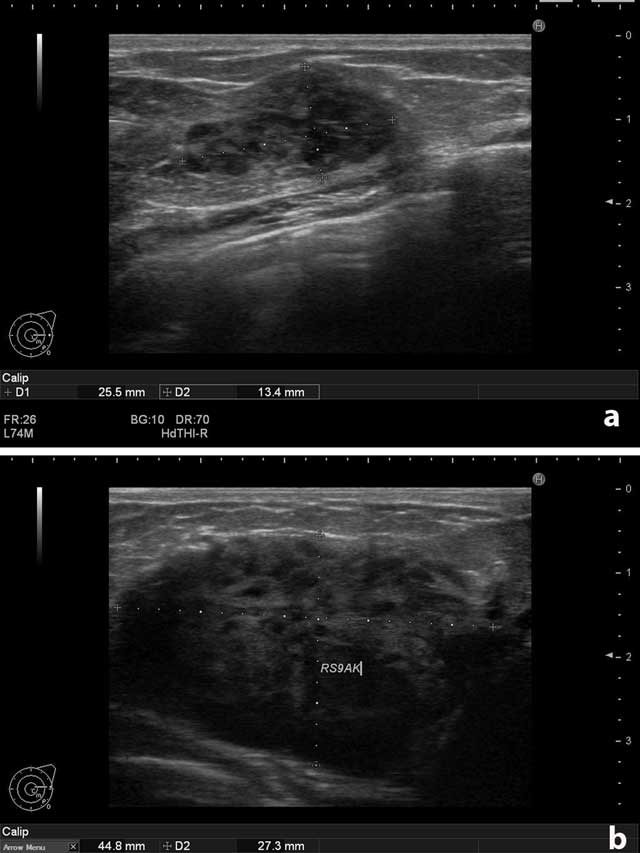

Figure 1

(a) Left breast. Solid, circumscribed mass. (b) Right breast. The largest solid mass measured 4.5 × 2.7 cm.